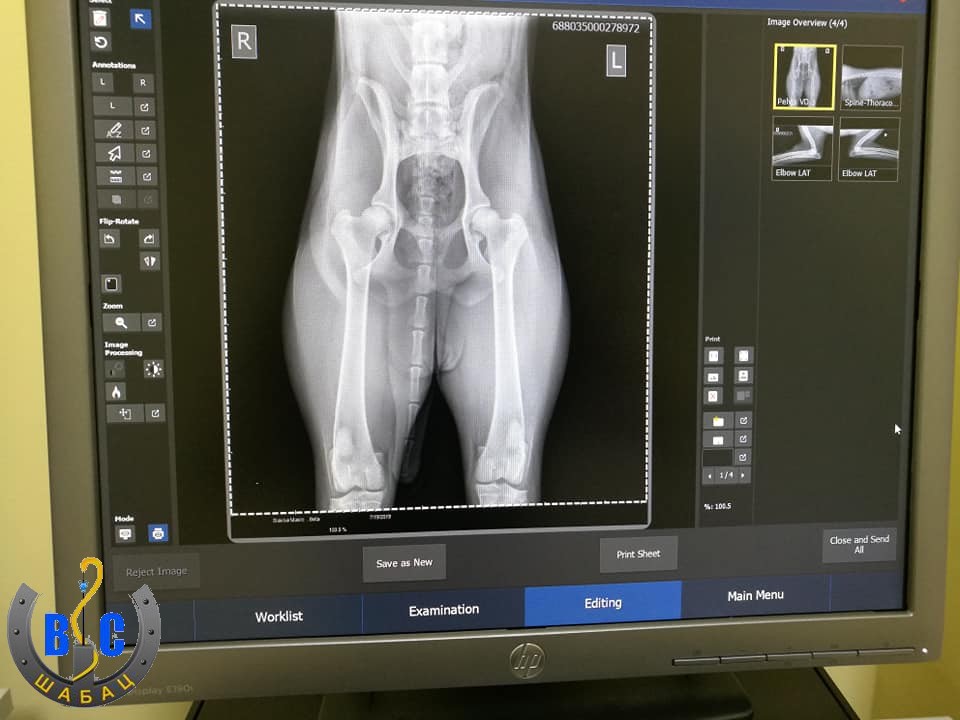

Rendgenska dijagnostika

Odnedavno u ambulanti Šabac moguće je izvršiti rendgensku dijagnostiku vaših kućnih ljubimaca, najsavremenijim digitalnim aparatom.